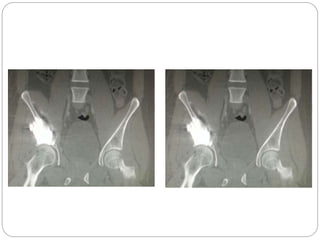

This document discusses 8 oncology cases. Case 1 involves a 40-year old female with right knee pain. Case 2 is a 28-year old male with a left subtrochantric fracture from a MVA who is now experiencing increasing left knee pain and swelling. Biopsy results showed high-grade osteosarcoma. Case 3 is a 30-year old female with breast cancer and bone metastases causing bilateral hip pain.